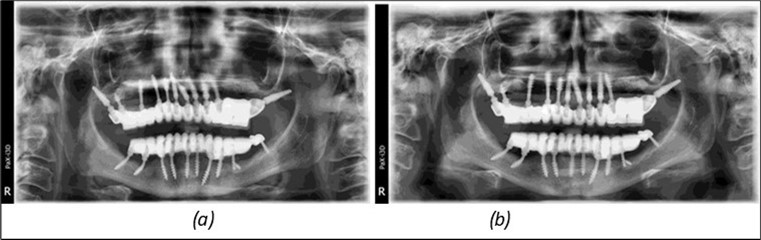

June 2022: Patient presented to our clinic for immediate-loading implant treatment At the time of presentation in 06. 2022, radiologically, advanced peri- implantitis is observed around the implants, with loss of native bone in the affected distal areas (Figure 1)

Figure 1.Panoramic overview picture before rehabilitation 06.2022

Figure 3.Panoramic pictures after removal of implants affected by peri-implantitis, extractions, alveolar crest regularization, and insertion of corticobasal and TPG implants (07.2022)

The results of rehabilitation treatment with corticobasal and compressive implants with a polished surface after the failure of two stage implants were highlighted over a period of 3 years and 3 months as being very good (Figure 14, Figure 15), with the patient completing a satisfaction survey in this regard. Certainly, it is necessary to continuemonitoring these results in the long term.